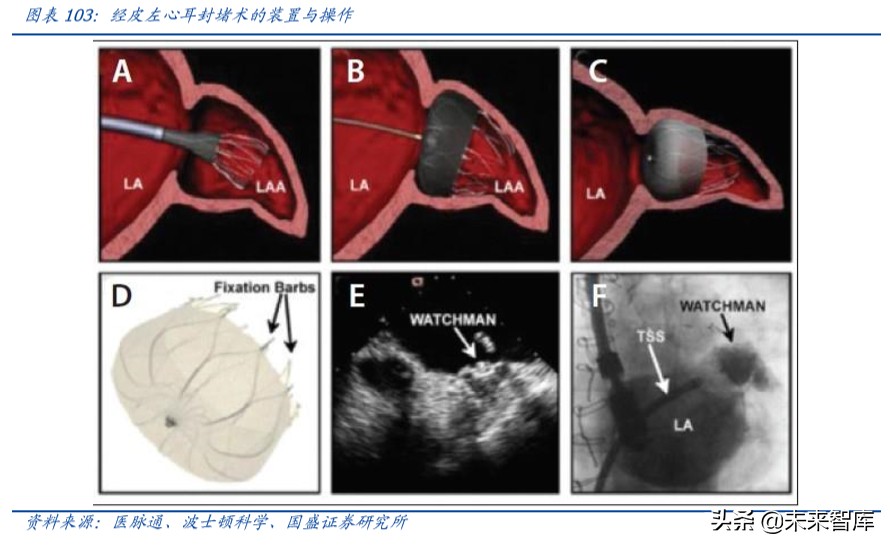

左心耳封堵器:有效预防房颤卒中,市场空间巨大

国内房颤患者数量巨大:左心耳由于具有特殊的生理位置,90%房颤患者卒中的血 栓来自心脏左心耳,对于无法长期口服抗凝药的患者,左心耳封堵是解决房颤患者 发生缺血性脑卒中的有效治疗方法。据《中国心血管病报告 2018》显示,中国≥35 岁居民的房颤患病率为 0.71%,目前全国房颤患者约有 990 万人。

左心耳封堵器有效降低卒中事件:CAP(Continued Access to PROTECT-AF)与 CAP2 (Continued Access to PREVAIL)是迄今为止左心耳封堵器(LAAC)样本量最大、 随访时间最长的注册研究。2019 年底这两项研究于 JACC 主刊发布其 5 年随访结 果:CAP 共纳入 566 例患者,平均随访 50.1 个月,CAP2 纳入 578 例患者,平均随 访 50.3 个月,总体手术成功率高达 94%。五年随访结果显示,两组患者出血性卒 中事件均显著降低,分别为 0.17/100 和 0.09/100 患者年,缺血性卒中的发生率为 1.30/100 和 2.20/100 患者年。全因卒中相比基于 CHA2DS2-VASc 评分的预测值显 著降低了 78%和 69%。这一研究结果充分揭示了 LAAC 的安全性和有效性,可作为 房颤血栓高危人群的优选治疗。

左心耳封堵在中国起步较晚但发展迅速:我国于 2014 年开展了左心耳封堵术的初 步应用,2015 年中国心房颤动认识和治疗建议中将左心耳封堵术推荐级别升高至 IIa,证据级别为 B 类,主要适用于不适合长期规范抗凝或在长期规范抗凝基础上仍 出现卒中事件或出血高危患者(HAS-BLED 评分在 3 分以上)。波士顿科学的 WATCHMAN™是目前全球唯一获得 FDA 认证的左心耳封堵器,截止 2018 年初美国 左心耳封堵例数已超过 15,000 例,波士顿科学预计 2018 年 LAAC 全球市场规模为 4亿美元,到2025年可达20亿美元,年复合增长超过25%。中国2017年WATCHMAN ™植入例数也超过了 1,500 例。目前开展左心耳封堵的单位已遍及全国 31 省市,接 近 200 家医院,而且手术量超过 100 台的中心已达 11 家。

左心耳封堵器潜在市场空间巨大:2016 年 6 月先健科技 LAmbre 左心耳封堵器获得 CFDA 批准后,2016 年营收 320 万,2017 年营收 2,110 万元, 2019 年上半年 LAmbre 左心耳封堵器营收 2590 万元,同比增长约 47.2%。目前我国仅 5 家公司产品获批 上市,进口器械有 Watchman 封堵器(美国波士顿科学)、 ACP 封堵器(圣犹达,美 国雅培收购),国产器械有 LAmbre 左心耳封堵器(先健科技)、北京迈迪顶峰医疗 的“左心耳闭合系统”和上海普实医疗的“左心耳封堵器系统”。乐普医疗目前左心 耳封堵器已通过 NMPA 注册申报,并通过 GMP 审核,预计 2020 年上市。预计未来 公司重磅产品上市,有望在封堵器领域逐步抢占市场份额,带来较大业绩增长。